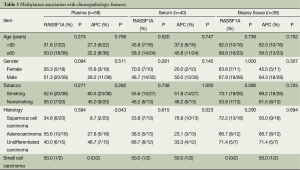

Association with clinicopathologic features

We analyzed the correlations between methylation status and clinicopathologic variables of the patients. As described in Table 3, no significant difference was found between methylation frequency and age, gender, tobacco or histology. There was an exception for methylation difference with histology of APC. The difference was significant with a P value less than 0.05 (P=0.039). APC methylation seemed to be more common in undifferentiated carcinoma.

Full table